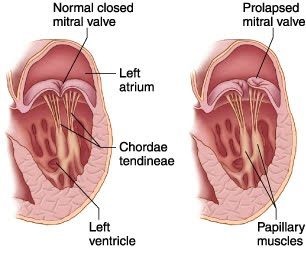

Nézzük meg a Google-ban az eredeti kép nyelvén kérésre "mitralis szelep prolapsus".

Több kép normát és prolapsust tartalmaz. A kép nagyítása egérkattintással. Piros aláhúzta a szelepek szimbólumát és a prolapszust, a sárga nyilak a vér áramlását mutatják a szisztolába:

Néhány világosabban értelmezett illusztráció.

A bal oldalon - Peter Griffin másik fordított üdvözlete a norma ábrázolásában:

Itt látható a mitrális szelep működésének ciklusa (nyitott - zárt) - ismét a szelep szélén lévő probléma: